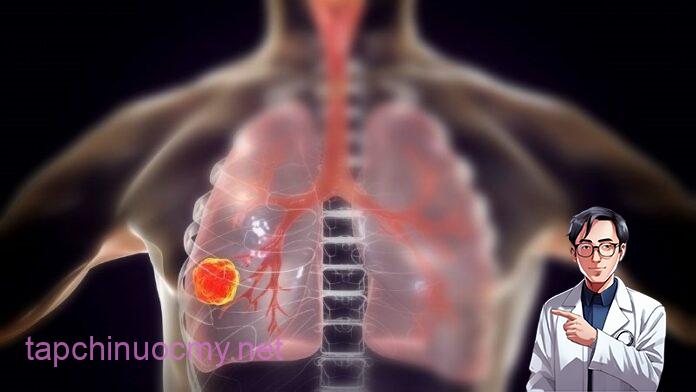

Ung thư đang ngày càng trở nên rất phổ biến và có xu hướng trẻ hóa rất cao. Trong đó, ung thư phổi là căn bệnh khá nhiều người không may mắc phải. Có nhiều triệu chứng cảnh báo ung thư phổi ở giai đoạn sớm, bạn nên lưu ý.

9 dấu hiệu ung thư phổi giai đoạn đầu, đừng lơ là kẻo di căn nguy hiểm

9 dấu hiệu ung thư phổi giai đoạn đầu, đừng lơ là kẻo di căn nguy hiểm